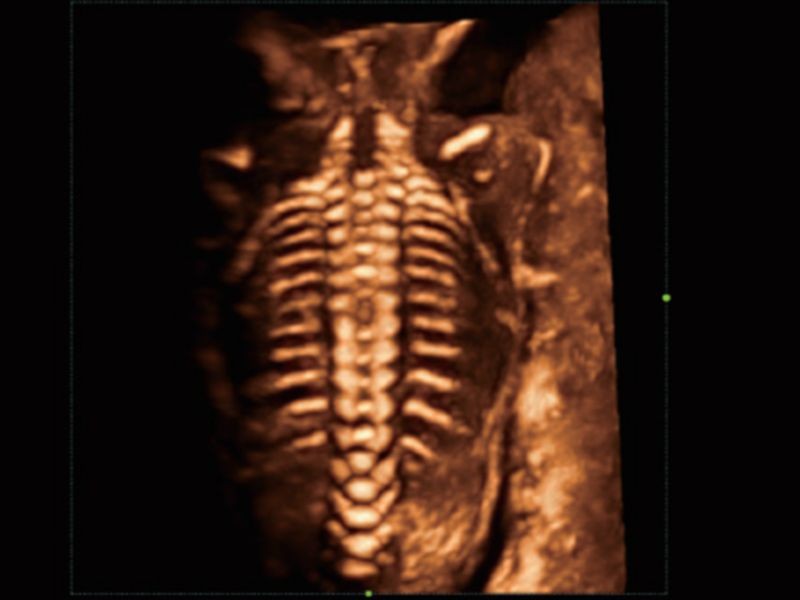

Estudo inteligente e preciso do SNC fetal - Smart Planes CNS

A tecnologia pioneira da Mindray permite a detecção totalmente automática e precisa dos planos mais significativos (MSP, TCP, TTP e TVP) e medições frequentemente usadas (BPD, HC, OFD, TCD, CM e LVW) do SNC fetal, resultando em melhor rendimento e menor dependência do usuário.